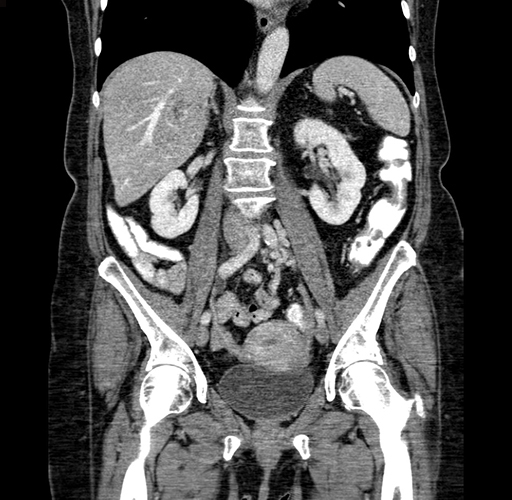

Pre-Chemo: Axial Venous

Pre-Chemo: Coronal Venous

Axial Venous

Coronal Venous

Imaging analysis

Based on your CT findings, which issue(s) would give reason for "planned slowing down moment(s)" in this case?

Considering a standard right hepatectomy procedure, what step(s) of the operation would you do differently in this case?